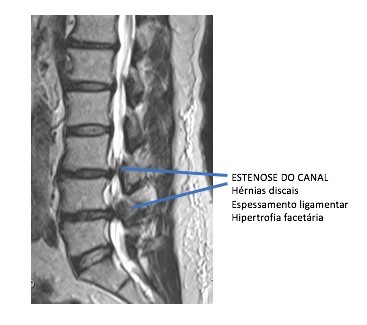

Com esse processo de degeneração, ocorre perda da altura discal e, de forma gradativa, mais carga é transferida para as articulações facetárias e leva a um processo de artrose e sinovite, com hipertrofia das facetas causando estenose foraminal.

A diminuição da altura discal também leva a uma frouxidão dos ligamentos ao redor das vértebras, causando movimentos anormais da vértebra e gerando instabilidade. Esse movimento das vértebras é conhecido como listeses.

Todo esse processo, junto, de abaulamento, protrusões ou herniações discais com hipertrofia das facetas articulares e espessamento dos ligamentos causa estenose do canal lombar.

O exame padrão ouro para o diagnóstico da estenose de canal lombar é a ressonância magnética da coluna lombar.

Ressonância magnética com estenose de canal lombar em 2 níveis L3L4 L4L5